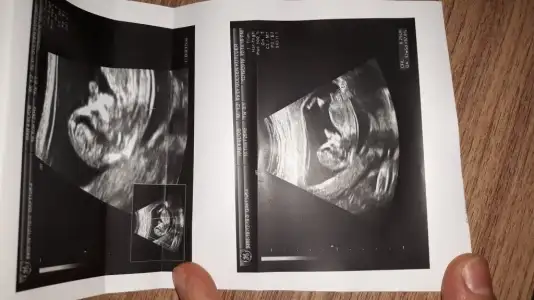

Kafa yapısı kız doktor 12 de gördüyse erkek olabilir bilemedim hayırlı evlat olsunHanımlar doktor gördü ama söylemedi sizce cinsiyetimiz nedir?

dr soylemeden siz gorun genital nub teorisi ( bebegin cinsiyeti)

Net degil 11 yada 12 hafta olmalıkizlar buna da yorum yapar misiniz. 10

Kız gibi 11 yada 12 hafta varsa paylaşınbunada bakarmısiniz lütfen

11 yada 12 hafta usg olmalıArkadaşlar merhaba . Belli oluyor mu acaba cinsiyeti yardimci olabilir mısınız

Nubu paralel inmiş pozisyon değiştirmediyse kız gibi ama kafa yapısı erkek

Kız gibi sanki nubu tam görünmüyor başka usg varmı

11+ yada 12+ usg paylaşın şimdilik kız sanki gibi gibi diyorum tekrar paylaşın

ErkekBenimkine de bakar mısınız 12 haftalik

Net değil12.haftayım benimkini de yorumlar mısınız?

KızMerhaba bayanlar ben yine doktora gittim ama öğrenemedik cinsiyeti. Bu da son usg. 12h5d

Kız gibiKızlar 11+6 benimkileride yorumlayabilirmisiniz çok merak ettim :)

Sanki nubu erkek gibiHanımlar doktor gördü ama söylemedi sizce cinsiyetimiz nedir?

Nubu paralel inmiş pozisyon değiştirmediyse kız gibi ama kafa yapısı erkek

D DeryakadirErkek sanki dedim çünki net degildi başka usg istedim evet bebeginiz 2. Usgde kız nubu boş görünüyor